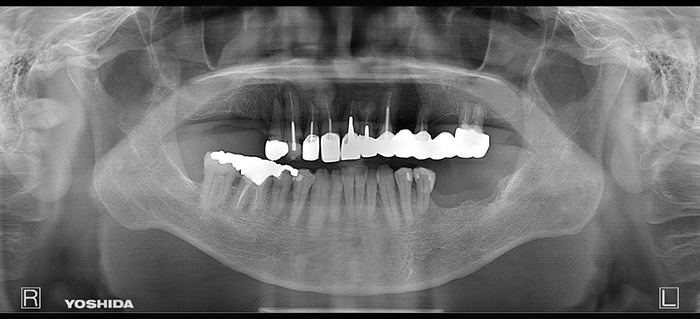

右上臼歯部2本・左下臼歯部2本にインプラント治療を行った症例です。

欠損部に対しインプラントを埋入し、咀嚼機能の回復と咬合バランスの改善を行いました。周囲歯への負担を抑えながら、固定性のある補綴装置により安定した噛み心地を目指した治療です。

【右上臼歯部インプラント治療】インプラント埋入手術および上部構造装着(2本)

【左下臼歯部インプラント治療】インプラント埋入手術および上部構造装着(2本)

【右上臼歯部インプラント治療】約4か月

【左下臼歯部インプラント治療】約3か月

【右上臼歯部インプラント治療】1本 ¥555,500(税込)

※本症例は2本

【左下臼歯部インプラント治療】1本 ¥555,500(税込)